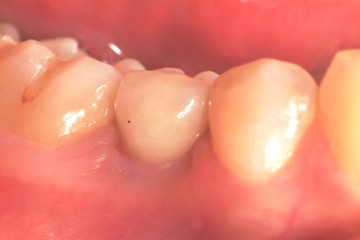

患者許小姐,左下第二小臼齒,因為深度蛀牙,因而牙齒被拔除(圖一、圖二、圖三),患者由於是一位高二學生,深怕缺牙久了若不處理,鄰牙可能倒過來(圖四),但若以傳統假牙修復,還需再磨完整的自然牙(圖五),經轉診至本診所尋求人工植牙。

圖三 |

圖四 |